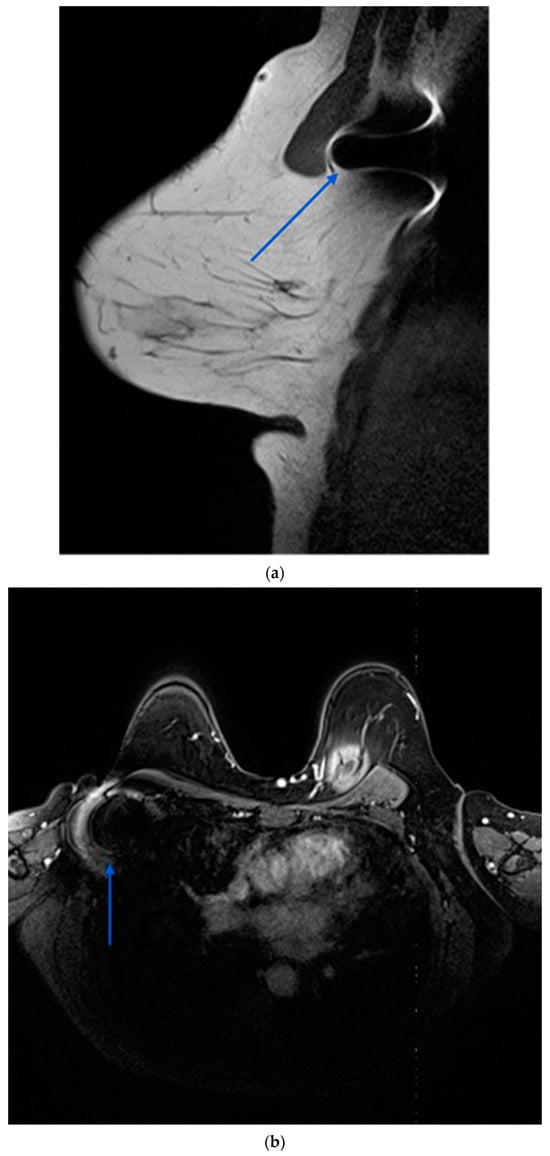

Several localisation technologies, including RSL, magnetic seeds (Magseed®), radio-frequency identification (RFID) tags, and SAVI SCOUT, offer advantages and limitations. Magseed®, a non-radioactive wireless marker, demonstrates high localisation rates and can be deployed at the time of biopsy, facilitating streamlined surgical procedures. However, it entails higher costs and may interfere with MRI interpretation due to the generation of significant void signals up to 4 cm (Figure 4) [,].

Figure 4.

Contrast enhanced MRI after completion of NST demonstrating ferromagnetic artefact (blue arrows) generated by a magnetic seed previously placed in a right pathological axillary lymph node. (a): sagittal view; (b): axial view.

A prominent limitation of the Magseed® system would be the requirement to remove all metal instruments from the surgical field during the use of the Sentimag probe. Furthermore, the ferromagnetic seeds interfere with MRI creating significant artefacts that can compromise the assessment of response to NST in both the axilla and the lateral aspect of the breast [,]. Additional drawbacks of this technology involve the necessity for frequent recalibration of the Sentimag due to interference from paramagnetic equipment, as well as its limited depth for accurate detection, which extends only up to 30 mm.